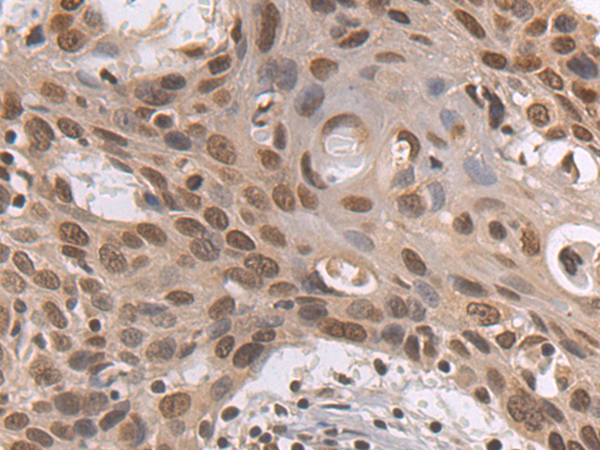

分类: 科研抗体货号: P07187别名: KIP1; MEN4; CDKN4; MEN1B; P27KIP1应用: WB,IHC反应种属: Human, Mouse